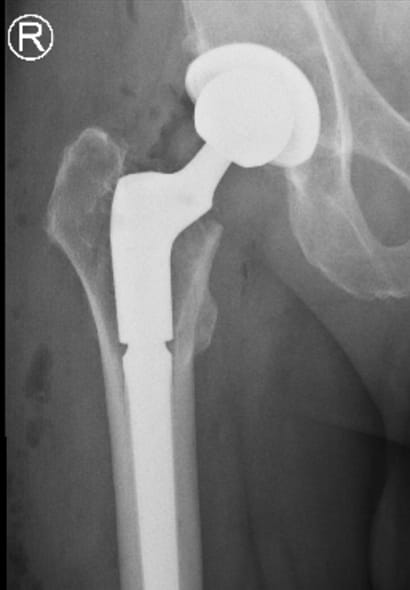

Mr J underwent a total hip replacement outside London 6 years ago. He had been suffering pain for over a year and noticed that his leg had shortened by over a centimetre. Investigations revealed he had a non-infective loosening of the original hip replacement stem. He underwent successful revision surgery under the care of Mr Simon Newman.